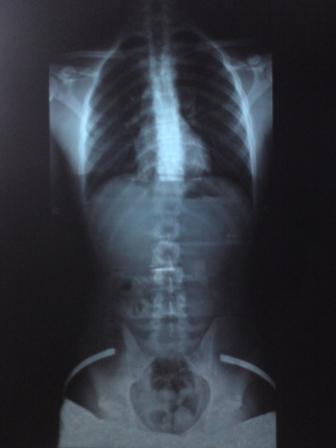

das hüftröngten ist ganz "frisch":

was sagt ihr zum beckenschiefstand bzw. beckenverwringung?

ich finds komisch, dass das steißbein (etwas schwer zu sehen) nicht genau hinter der symphyse (wo hüfte links und rechts vorne zusammenkommen) liegt, sonder links.

ich versteh nach wie vor nicht, warum ich mit einer einigermaßen geringen skoliose einen beckenschiefstand von 7 mm haben kann ...

der beckenschiefstand bzw. verwringung macht mir deswegen sorgen, weil ich eben schon einen prolaps über dem kreuzbein l5/s1 habe.

thorakal linkskonvex;

ausgemessen wurden ca. 13 grad bws und 6 grad lws.

röngtenbilder schauen nicht dramatisch aus, machen mir aber immense beschwerden, vorallem in der bws und in der lws der ständige "druckschmerz" oberhalb der rechten beckenschaufel.

beachtenswert is irgendwie der untschied bei der lws zw den beiden röngtenganzaufnahmen.